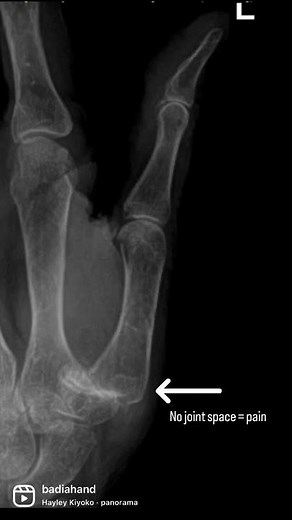

Diesel - CMC Joint

Replacement - Basal Joint

Arthroplasty - Basal Thumb

Restaurant - CMC Arthritis